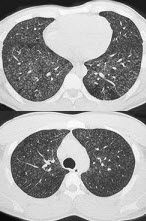

23、单项选择题

女,34岁,新月体肾炎患者,最近咳嗽咯血,第一次行胸片检查考虑为双下肺感染,抗感染治疗后无明显好转,症状加重,4天后复查并行CT检查如图,应考虑为()

A.肺泡蛋白沉着症

B.肺含铁血黄素沉着症

C.双下肺肺炎

D.肺出血肾炎综合征

E.韦格肉芽肿